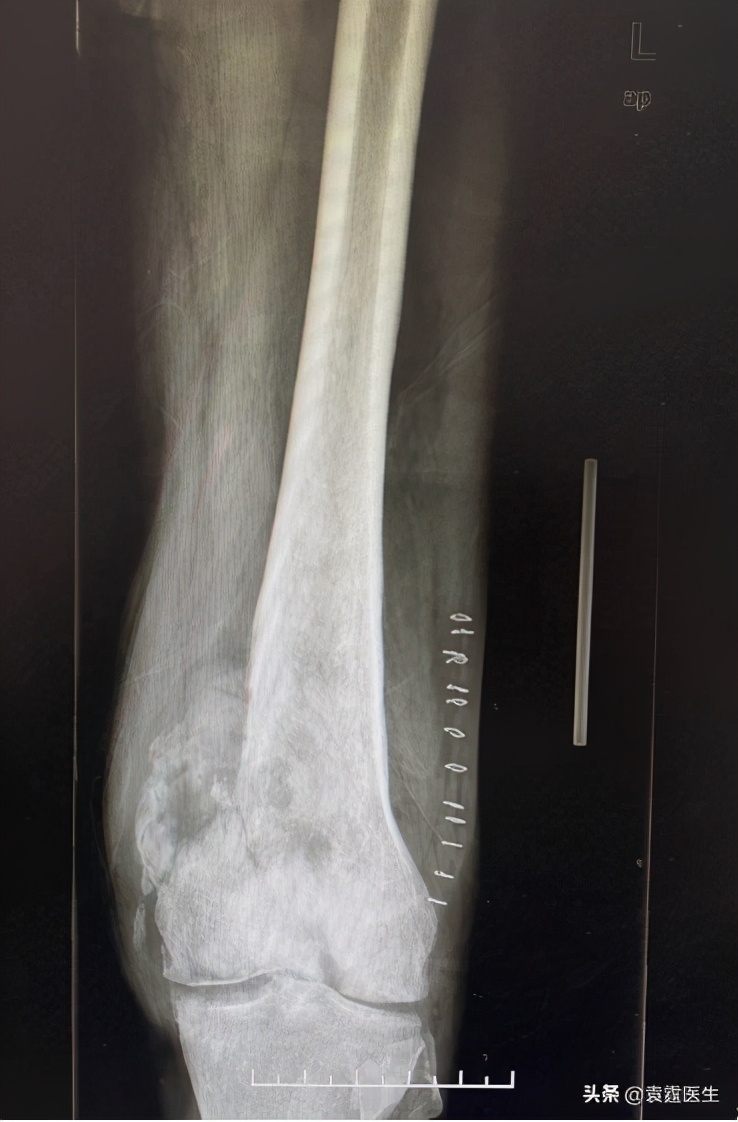

X线

梗死相关肉瘤是罕见的。它们似乎出现在长期存在的成熟梗塞中,特别是发生在下肢的梗塞。发生梗死相关肉瘤的许多患者没有确定骨坏死发展的危险因素,但是大部分患者都有多发性骨梗死。疼痛是最常见的表现症状,在影像学上当骨质疏松和骨质破坏的骨质疏松(或矿化)区域不明确时,会出现在骨梗死的旁边。图1:X线影像学表现为股骨远端局部病变,远端骨折后。但当怀疑梗死相关肉瘤时,推荐使用图2,3:MRI来确认肉瘤的发展,并显示骨和软组织侵袭的程度,更能明确诊断,避免误诊。